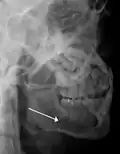

lateral oblique image demonstrating a fractured mandible.

Traditionally, plain films of the mandible would be exposed but had lower sensitivity and specificity owing to overlap of structures. Views included AP (for parasymphsis), lateral oblique (body, ramus, angle, coronoid process) and Towne's (condyle) views. Condylar fractures can be especially difficult to identify, depending on the direction of condylar displacement or dislocation so multiple views of it are usually examined with two views at perpendicular angles.[11]